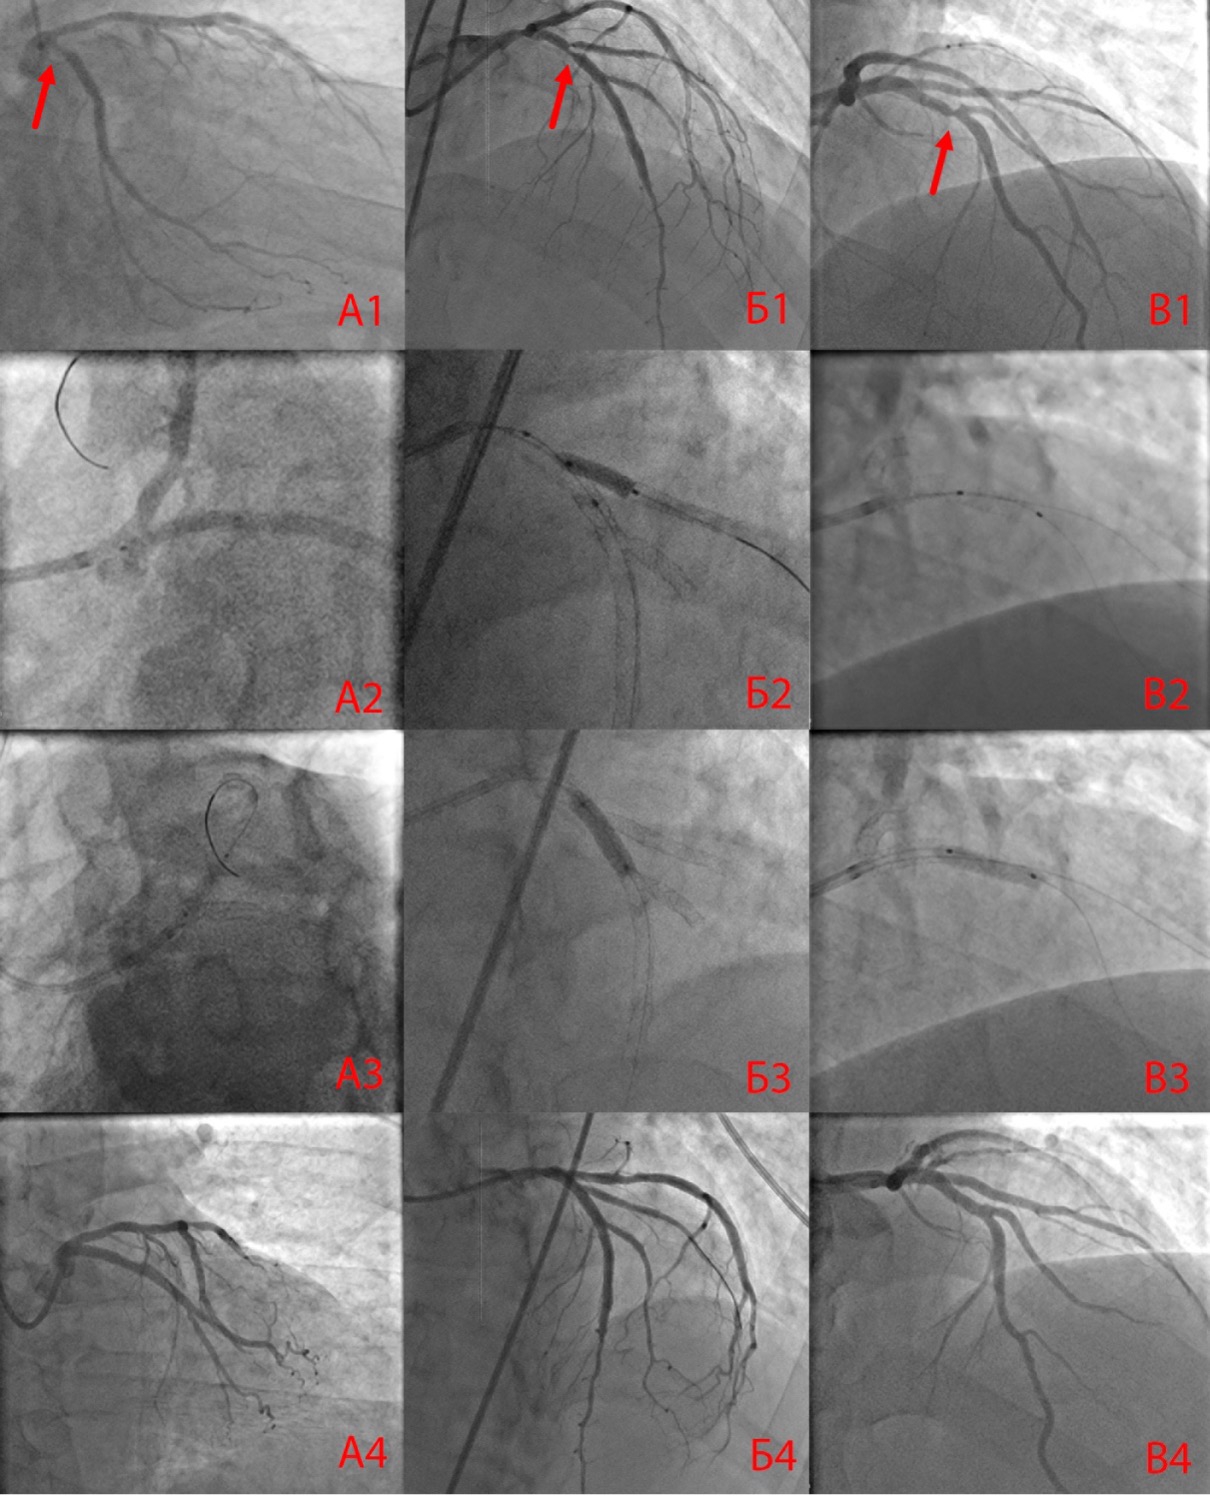

According to the quantitative analysis at the end of the intervention, residual stenosis of the MB was statistically significantly more evident in group 3 (p=0.002). Residual stenosis of the SB was less in group 2 (p=0.001, Table 3). The immediate results of PCI are presented in Figure 2.

Fig. 2. The immediate result of percutaneous coronary intervention with a one-stent method of correcting bifurcation in-stent restenosis (A1–A4), with a two-stent method (B1–B4) and using a drug-eluting balloon catheter (C1–C4).